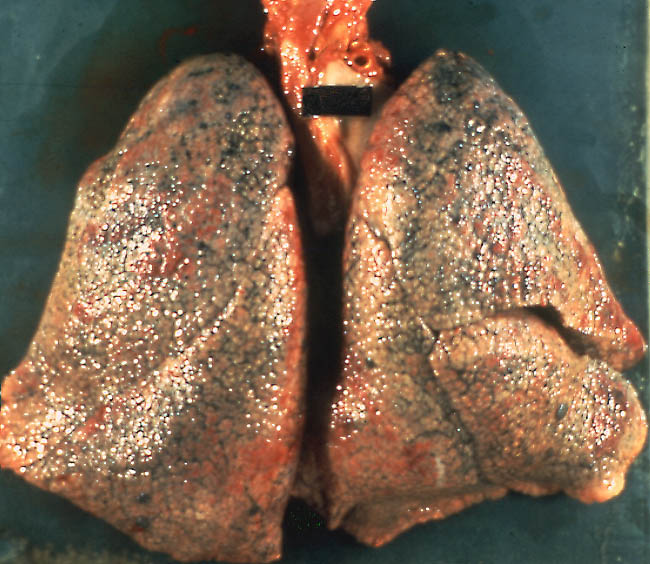

_正常肺部與肺纖維化X線對比

_雙肺肺纖維化的

_雙肺肺纖維化肺灶